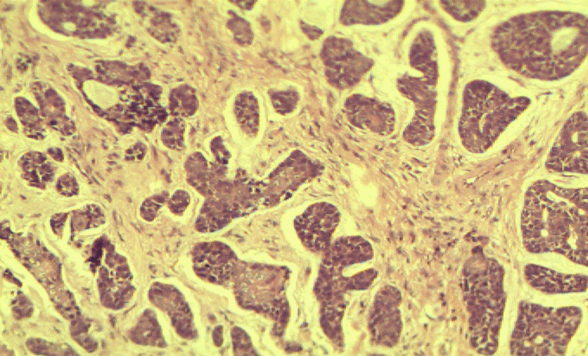

A soft tissue specimen of size 1.5x1 cm was taken and subjected to histology. 4x view revealed parakeratinized stratified squamous surface epithelium with tumor cells in the fibrocellular connective tissue stroma. 20x view showed aggregates of hyperchromatic tumor cells having scanty cytoplasm with central cystic spaces in the fibrocellular connective tissue stroma (Figure 4). Thus histopathological diagnosis confirmed it as adenoid cystic carcinoma.

Figure 4: Histological picture showing aggregates of hyperchromatic tumor cells having scanty cytoplasm with central cystic spaces in the fibrocellular connective tissue stroma.